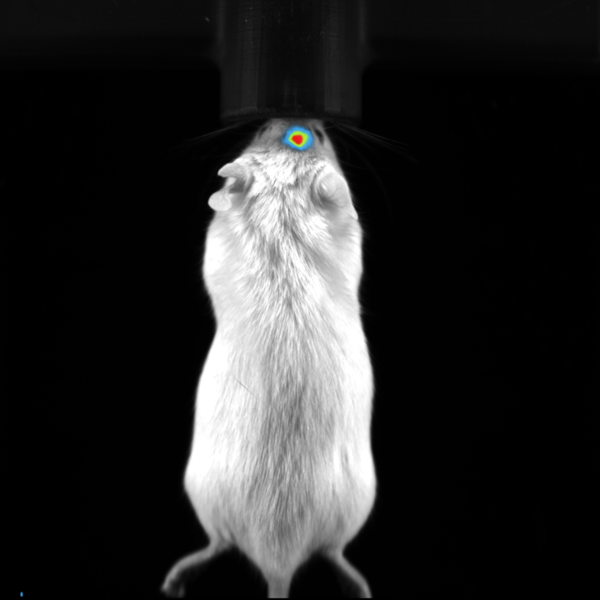

Bioluminescence imaging

Luciferase-expressing or secreting molecules in the target tissue can be found via bioluminescence imaging.

Subcutaneous tumor expressing firefly luciferase. Image Credit: Scintica Instrumentation Inc

BLI Image of Orthotropic Brain Tumor in Mouse. Image Credit: Scintica Instrumentation Inc